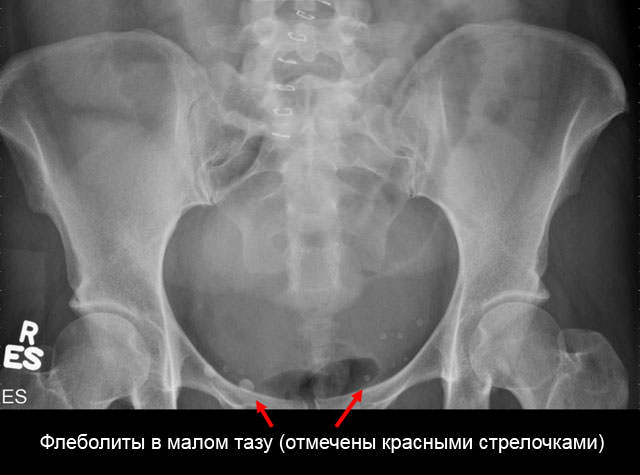

Рентгенограмма, как метод диагностики, подразумевает получение постоянного негативного изображения исследуемого объекта на пленке с помощью рентгеновского излучения. Часто этот способ называют просто «рентгеновский снимок».

При проведении рентгенограммы флеболиты вен обнаруживаются в качестве множественных теней. Чтобы отличить венозные камни от конкрементов (камней плотной структуры), специалисты исследуют не только структуру и форму образований, но и место их расположения.

Часто обнаружение флеболитов – совершенно неожиданная находка при рентгенологических или томографических исследованиях, реже их можно обнаружить при ультразвуковых исследованиях. Обычно подобные образования являются случайным открытием и никак не беспокоят пациента. Называть флеболитиаз заболеванием в корне неверно, поскольку это явление совершенно безопасно.

Химический состав флеболитов и конкрементов мочеточников идентичен, что придает им такую же плотность тени на рентгенограммах.

Проблемы возникают при обнаружении таких образований на рентгенограмме. Так как плотность, форма, размер, расположение флеболита и камней в мочевыводящей системе идентичны, то нужно знать отличительные признаки этих заболеваний:

Флеболиты таза представляют собой кровяной сгусток, который со временем превратился в камень за счет пропитывания солями кальция. Чаще всего не дает клинической симптоматики, обнаруживается у женщин при прохождении рентгенологического обследования. Внешний вид таких образований нередко ошибочно расценивается как камень мочеточника, почек или мочевого пузыря.